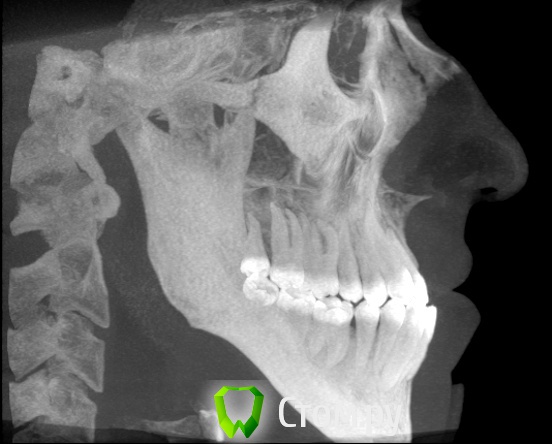

Здравствуйте! Мне 27 лет.  Очень вас прошу дать свою оценку моей ситуации. У меня сложная ситуация, я уже обошел многие ортодонтические кабинеты своего города и все говорят разное. У меня мезальный прикус, но своим профилем я доволен, я всем доволен, кроме того что у меня неправильный прикус (верхние резцы заходили за нижние и были вогнуты вовнутрь) и кривые зубки.Сейчас по рекомендации одного ортодонта ношу капу чтобы верхние резцы перепрыгнули, но теперь и это занятие меня сильно беспокоит, хотя ношу всего месяц и уже попадает зуб на зуб. Главный мой вопрос таков: "Возможно ли в моей ситуации исправить прикус без операции?" Спасибо за ответы!